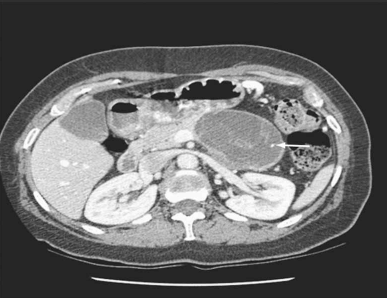

Mulher de 39 anos procurou atendimento por dor abdominal vaga, de fraca intensidade, há 4 meses. No exame físico, detectou-se uma massa abdominal de limites imprecisos e pouco dolorosa. Foi solicitada tomografia abdominal (imagem demonstrada). O exame histológico do material colhido por punção aspirativa com agulha fina revelou níveis baixos de amilase, presença de células ricas em mucina e estroma similar ao do ovário. O diagnóstico da paciente é:

Enunciado 4099950-1

(TOWNSEND JR., C. M.; BEAUCHAMP, R.D.; B. EVERS, M. AND MATTOX, K.L. SABISTON - Tratado de Cirurgia. 20ª Edição, Ed. Elsevier, 2019, Cap. 55, pg. 2395)